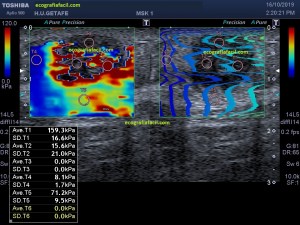

En la imagen 3 ves una imagen de un lipoma, mide 7 cms, la huella de la sonda mide 5cms, la «panoramic view» posee una regla centimetrada que sigue el contorno de la imagen, justo en la profundidad de la misma y lo marca la flecha amarilla. La profundidad la marca la flecha roja y la flecha blanca marca el rango centimetral de los 5cms, fíjate que la línea blanca es ligeramente mayor cada 5 cms. Sirve de referencia, como en la imagen 4 donde ves una colección en el glúteo de más de 10 cms.

Técnicamente es lo mismo, ambos dispositivos hacen una suma de imágenes que se plasman en un resultado final estupendo. Toda la escena más pequeña, pero más alargada que te da percepción de toda la magnitud de aquello que pretendes estudiar, te quita algo de detalle, pero te sirve para medir perfectamente y además puedes incrementar y mover la imagen con tu track ball…

Podemos medir valores superiores a los 15cms con alta calidad de imagen…podemos llegar a medir valores por encima de los 25 cms…es verdad que no todos los equipos tienen este ajuste ecográfico, es decir, es una aplicación y por tanto hay que pagarla.